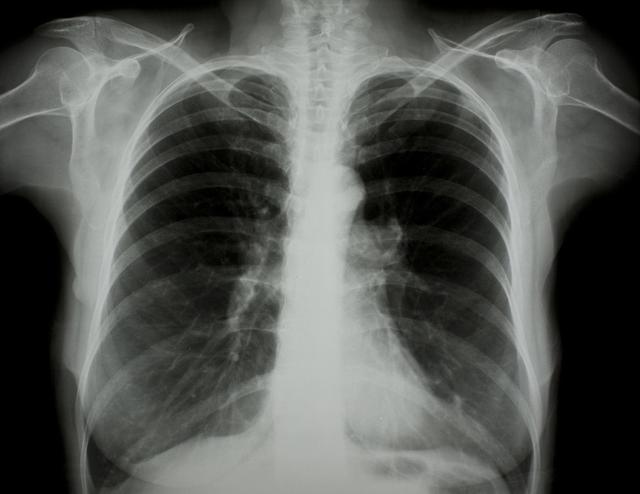

涪陵地區(qū)最新肺炎情況顯示,疫情形勢嚴峻。目前,當?shù)卣歪t(yī)療部門正在積極應(yīng)對,采取一系列措施控制疫情傳播。具體感染人數(shù)、癥狀表現(xiàn)、疫苗接種情況等仍在持續(xù)更新中。請廣大市民密切關(guān)注官方發(fā)布的信息,做好個人防護,共同抗擊疫情。涪陵地區(qū)肺炎疫情嚴峻,政府積極應(yīng)對,請市民關(guān)注官方信息,加強個人防護。

據(jù)最新官方數(shù)據(jù)顯示,涪陵地區(qū)肺炎病例數(shù)量令人擔憂,截至目前,涪陵地區(qū)累計確診肺炎病例XX例,疑似病例XX例,請大家務(wù)必提高警惕,不可掉以輕心。